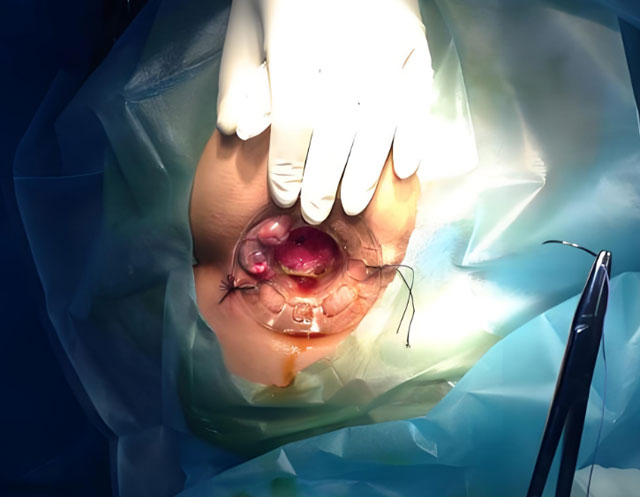

· 手術治療:當混合痔脫出不能回納、便血嚴重導致貧血或經常發作影響生活品質時,通常需要考慮手術治療。常見的手術方式有外剝內紮術、吻合器痔上黏膜環切術(PPH)、選擇性痔上黏膜吻合術(TST)等。醫生會根據患者的具體情況選擇合適的手術方法。